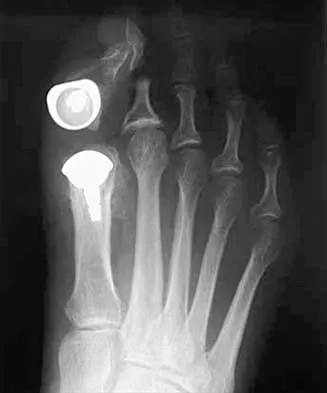

Ace your 2026 Orthopedic Foot and Ankle boards. Includes high-yield MCQs, surgical techniques, updated clinic…